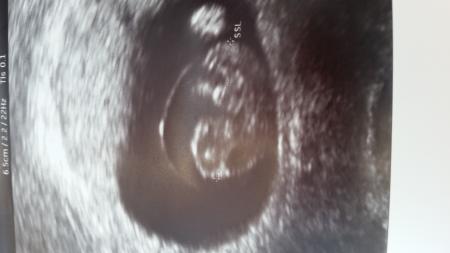

Ich bin soo verliebt ich mache mir immer so viele Sorgen und dabei ist dann doch alles gut und mein babylein ist bestens entwickelt Mein Puschel hat jetzt eine Größe von 1,6cm :)) ich hänge euch noch ein Bild an :) einen schönen sonnigen tag euch noch

Bild zu Glücklich mit US Bild :) - Forum für Januar - Mamis